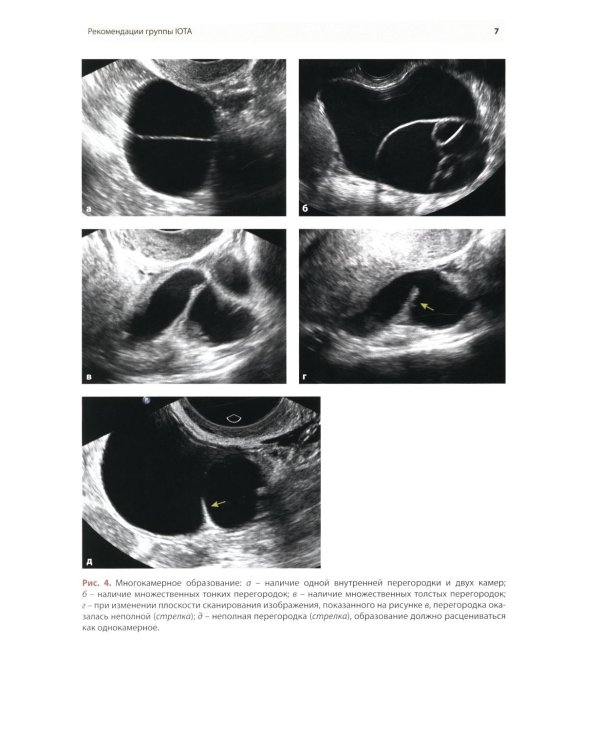

Методические рекомендации по стандартизации ультразвукового исследования с целью своевременной диагностики опухолевого процесса. Книга также включает вопросы дифференциальной диагностики физиологических изменений яичников, опухолевидных и опухолевых заболеваний и маршрутизации пациенток. Утверждено в качестве методических рекомендаций для проведения циклов первичной переподготовки врачей по ультразвуковой диагностике, тематического усовершенствования «Ультразвуковая диагностика в гинекологии», общего усовершенствования, ординаторов и аспирантов, проходящих обучение по направлению «Ультразвуковая диагностика, акушерство и гинекология».| Издательство | МЕДпресс-информ |